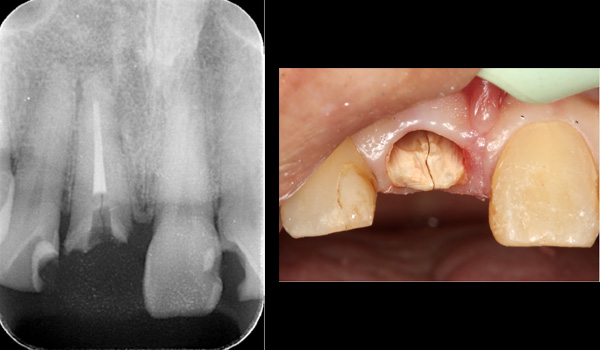

| 主訴 | 右下の歯が割れてしまったのでインプラントをして欲しい |

| 治療期間 | 約6ヶ月 |

| 費用 | 1,100,000円 |

| 治療内容 | インプラント、骨造成、結合組織移植、セラミック修復 |

| 治療に伴うリスク | インプラント周囲炎 セラミックの破折、脱離 |